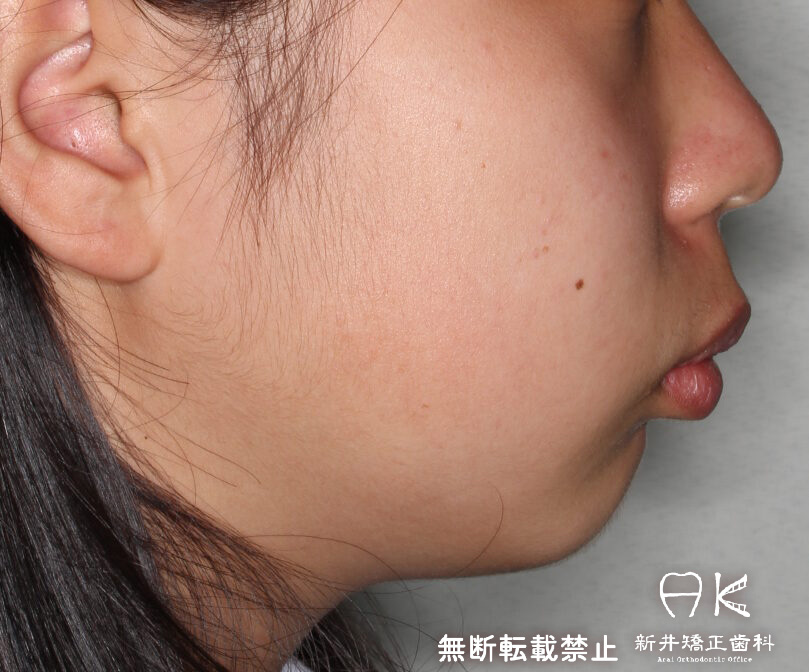

ハーフリンガルでの叢生(ガチャ歯)とすれ違い咬合と口元の突出感の治療(正面と横顔の変化あり)

治療前後の解説

| 治療前 | でこぼこしている歯による歯磨きのやりにくさや、奥歯がしっかり咬んでいない鋏状咬合(すれ違い咬合)。 出っ歯による口の閉じにくさ(口唇閉鎖不全)と、正面から見た時のオトガイ部にできる梅干し様のシワやイーラインから飛び出た口元(口ゴボ)。 機能面も審美面も気にしていた患者さんです。 治療中もなるべく装置を目立たせたくないため、ハーフリンガルでの治療となりました。 |

| 治療後 | 上下の歯がお互いにはまり込み、全体的に緊密な咬み合わせになっています。 出っ歯が治り、口元の突出感が改善されて綺麗なEラインを獲得しました。 すれ違い咬合や叢生(歯のでこぼこ)も治って歯磨きがしやすく、嚙みやすい状態になっています。 |